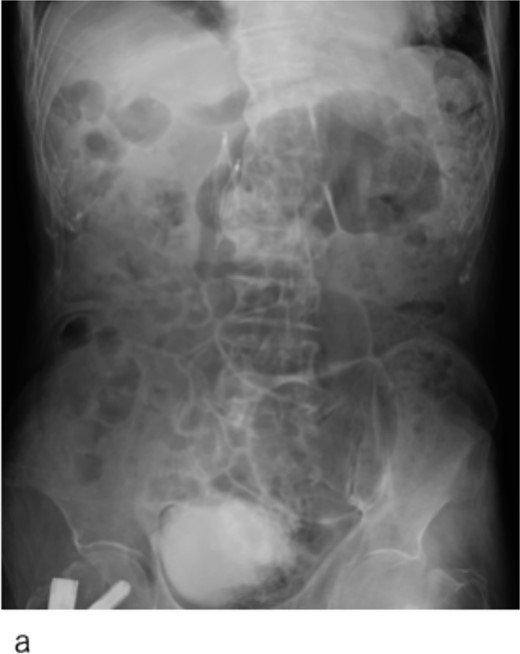

An IVCF was inserted into the inferior vena cava (IVC) using the right internal jugular venous approach. After performing IVC venography (Fig. 2a) using a driver sheath, the IVCF was attempted to deployed. However, the IVCF did not open (Fig. 2b). To retrieve the unopened filter, a plunger was pulled; however, the IVCF and plunger detached (Fig. 2c). We attempted to remove the IVCF via a right femoral venous approach using a snare. However, the snare did not pass through the IVCF because the tip of the leg was attached to the IVC wall or gonadal vein ostium. The hemodynamics of the patient worsened during the procedure. Therefore, we decided to quit additional endovascular retrieval and place a new IVCF. A new IVCF was placed to hold the unopened IVCF at the proximal (head) portion of the unopened IVCF through a right jugular approach (Fig. 2d). An unopened IVCF was placed with pulling the delivery sheath (Fig. 3).

Abdominal X-ray image after the surgery. Two inferior vena cava filters are placed.